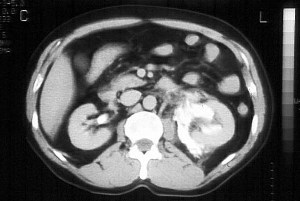

CASO 1: Paciente de 58 años que se realiza TC de abdomen tras historia de dolor abdominal y hematuria microscópica. Refiere pérdida de peso en las últimas semanas.

Estamos ante una afectación bilateral del espacio perirrenal, más evidente en el lado derecho, por masas de densidad de partes blandas en un paciente con numerosas adenopatías retroperitoneales. Estaría indicado realizar una biopsia, ya que el diagnóstico principal orienta hacia un síndrome linfoproliferativo, espcialmente linfoma no Hodgkin tipo B.